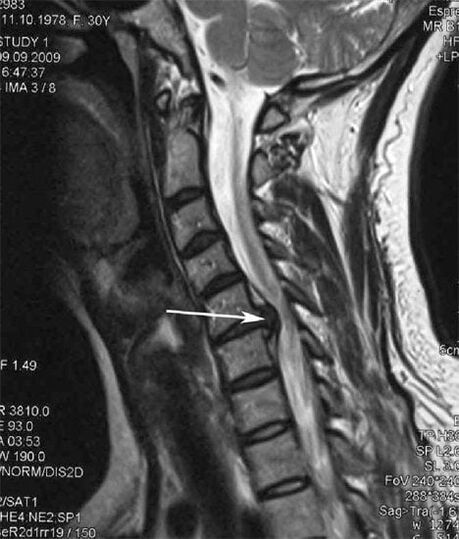

In the initial stages, osteochondrosis is detected by MRI.Later, the pathology can be diagnosed using radiography.X-rays of the cervical spine show a decrease in the distance between the vertebrae, pathological changes in the facet joints and osteophytosis.

Many people complain that they cannot turn their neck due to severe pain that occurs after suddenly lifting something heavy.This phenomenon indicates the formation of a herniated disc.The cause of pain in the back, neck and upper extremity is the pinching of one of the nerve roots coming out of the spinal cord.